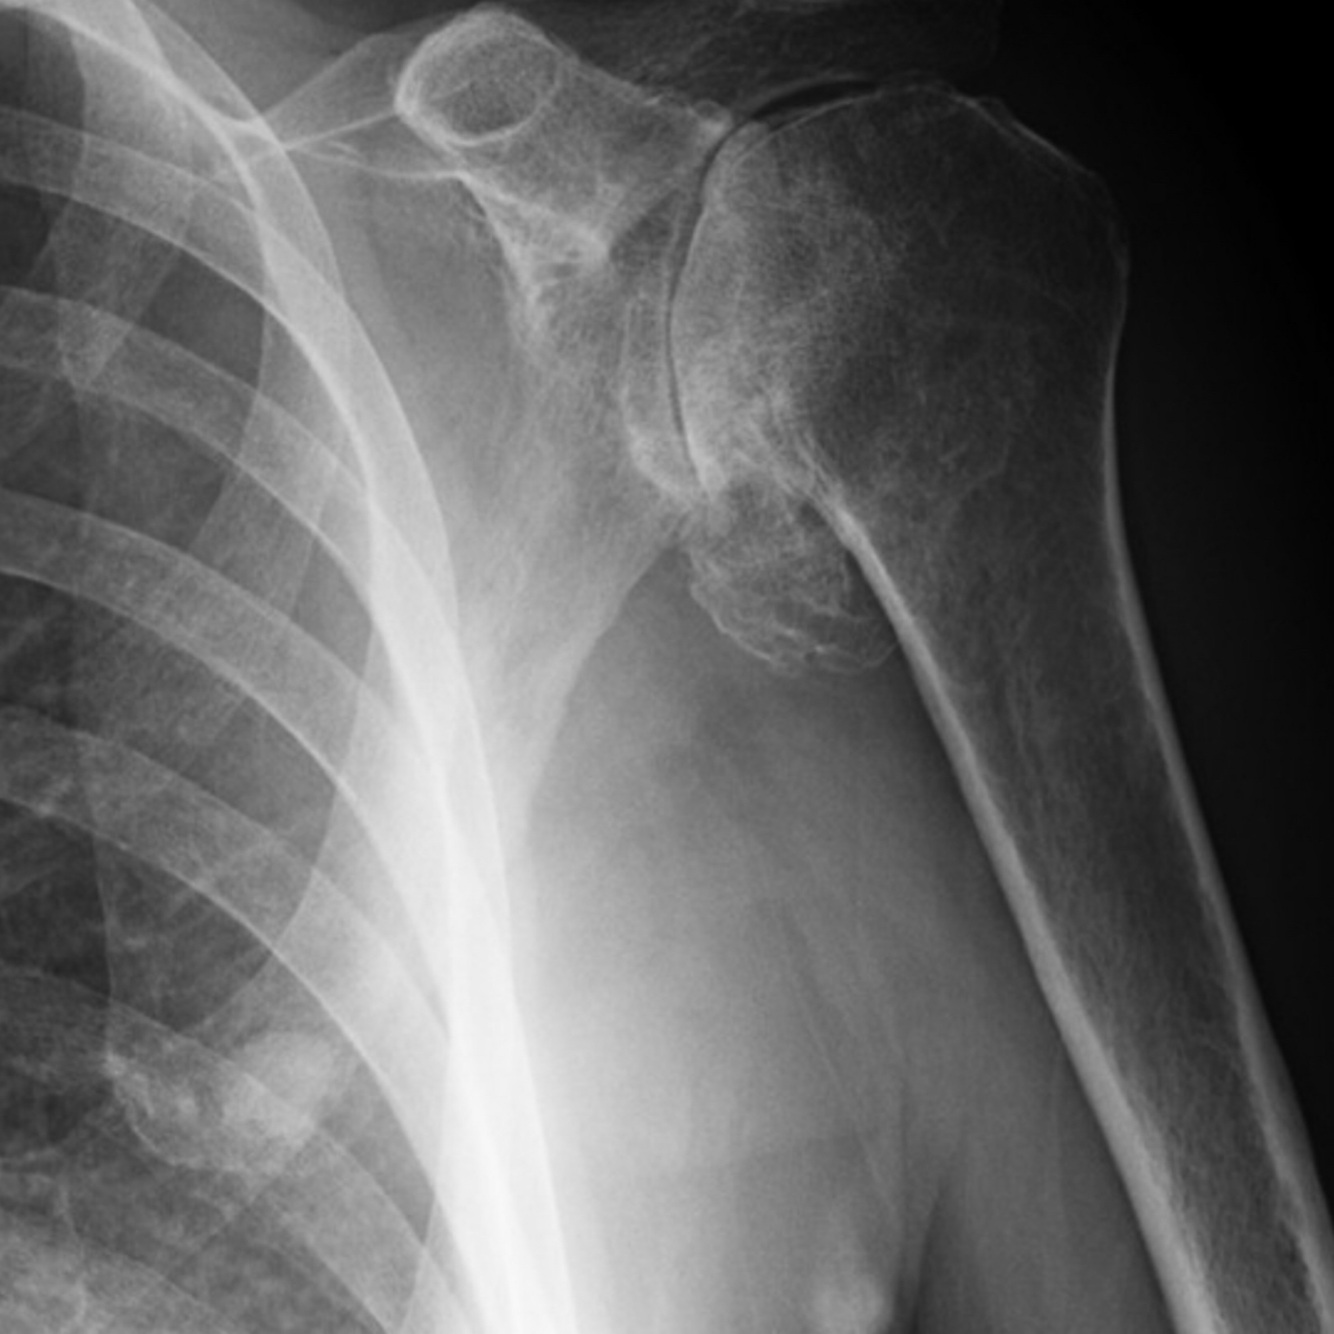

De acuerdo a la clasificación de Neer, ¿a que tipo corresponde esta fractura? De acuerdo a la clasificación de Neer, ¿a que tipo corresponde esta fractura? Pregunta 8 opciones: Multifragmentada Articular 2 partes 3 partes

3 partes